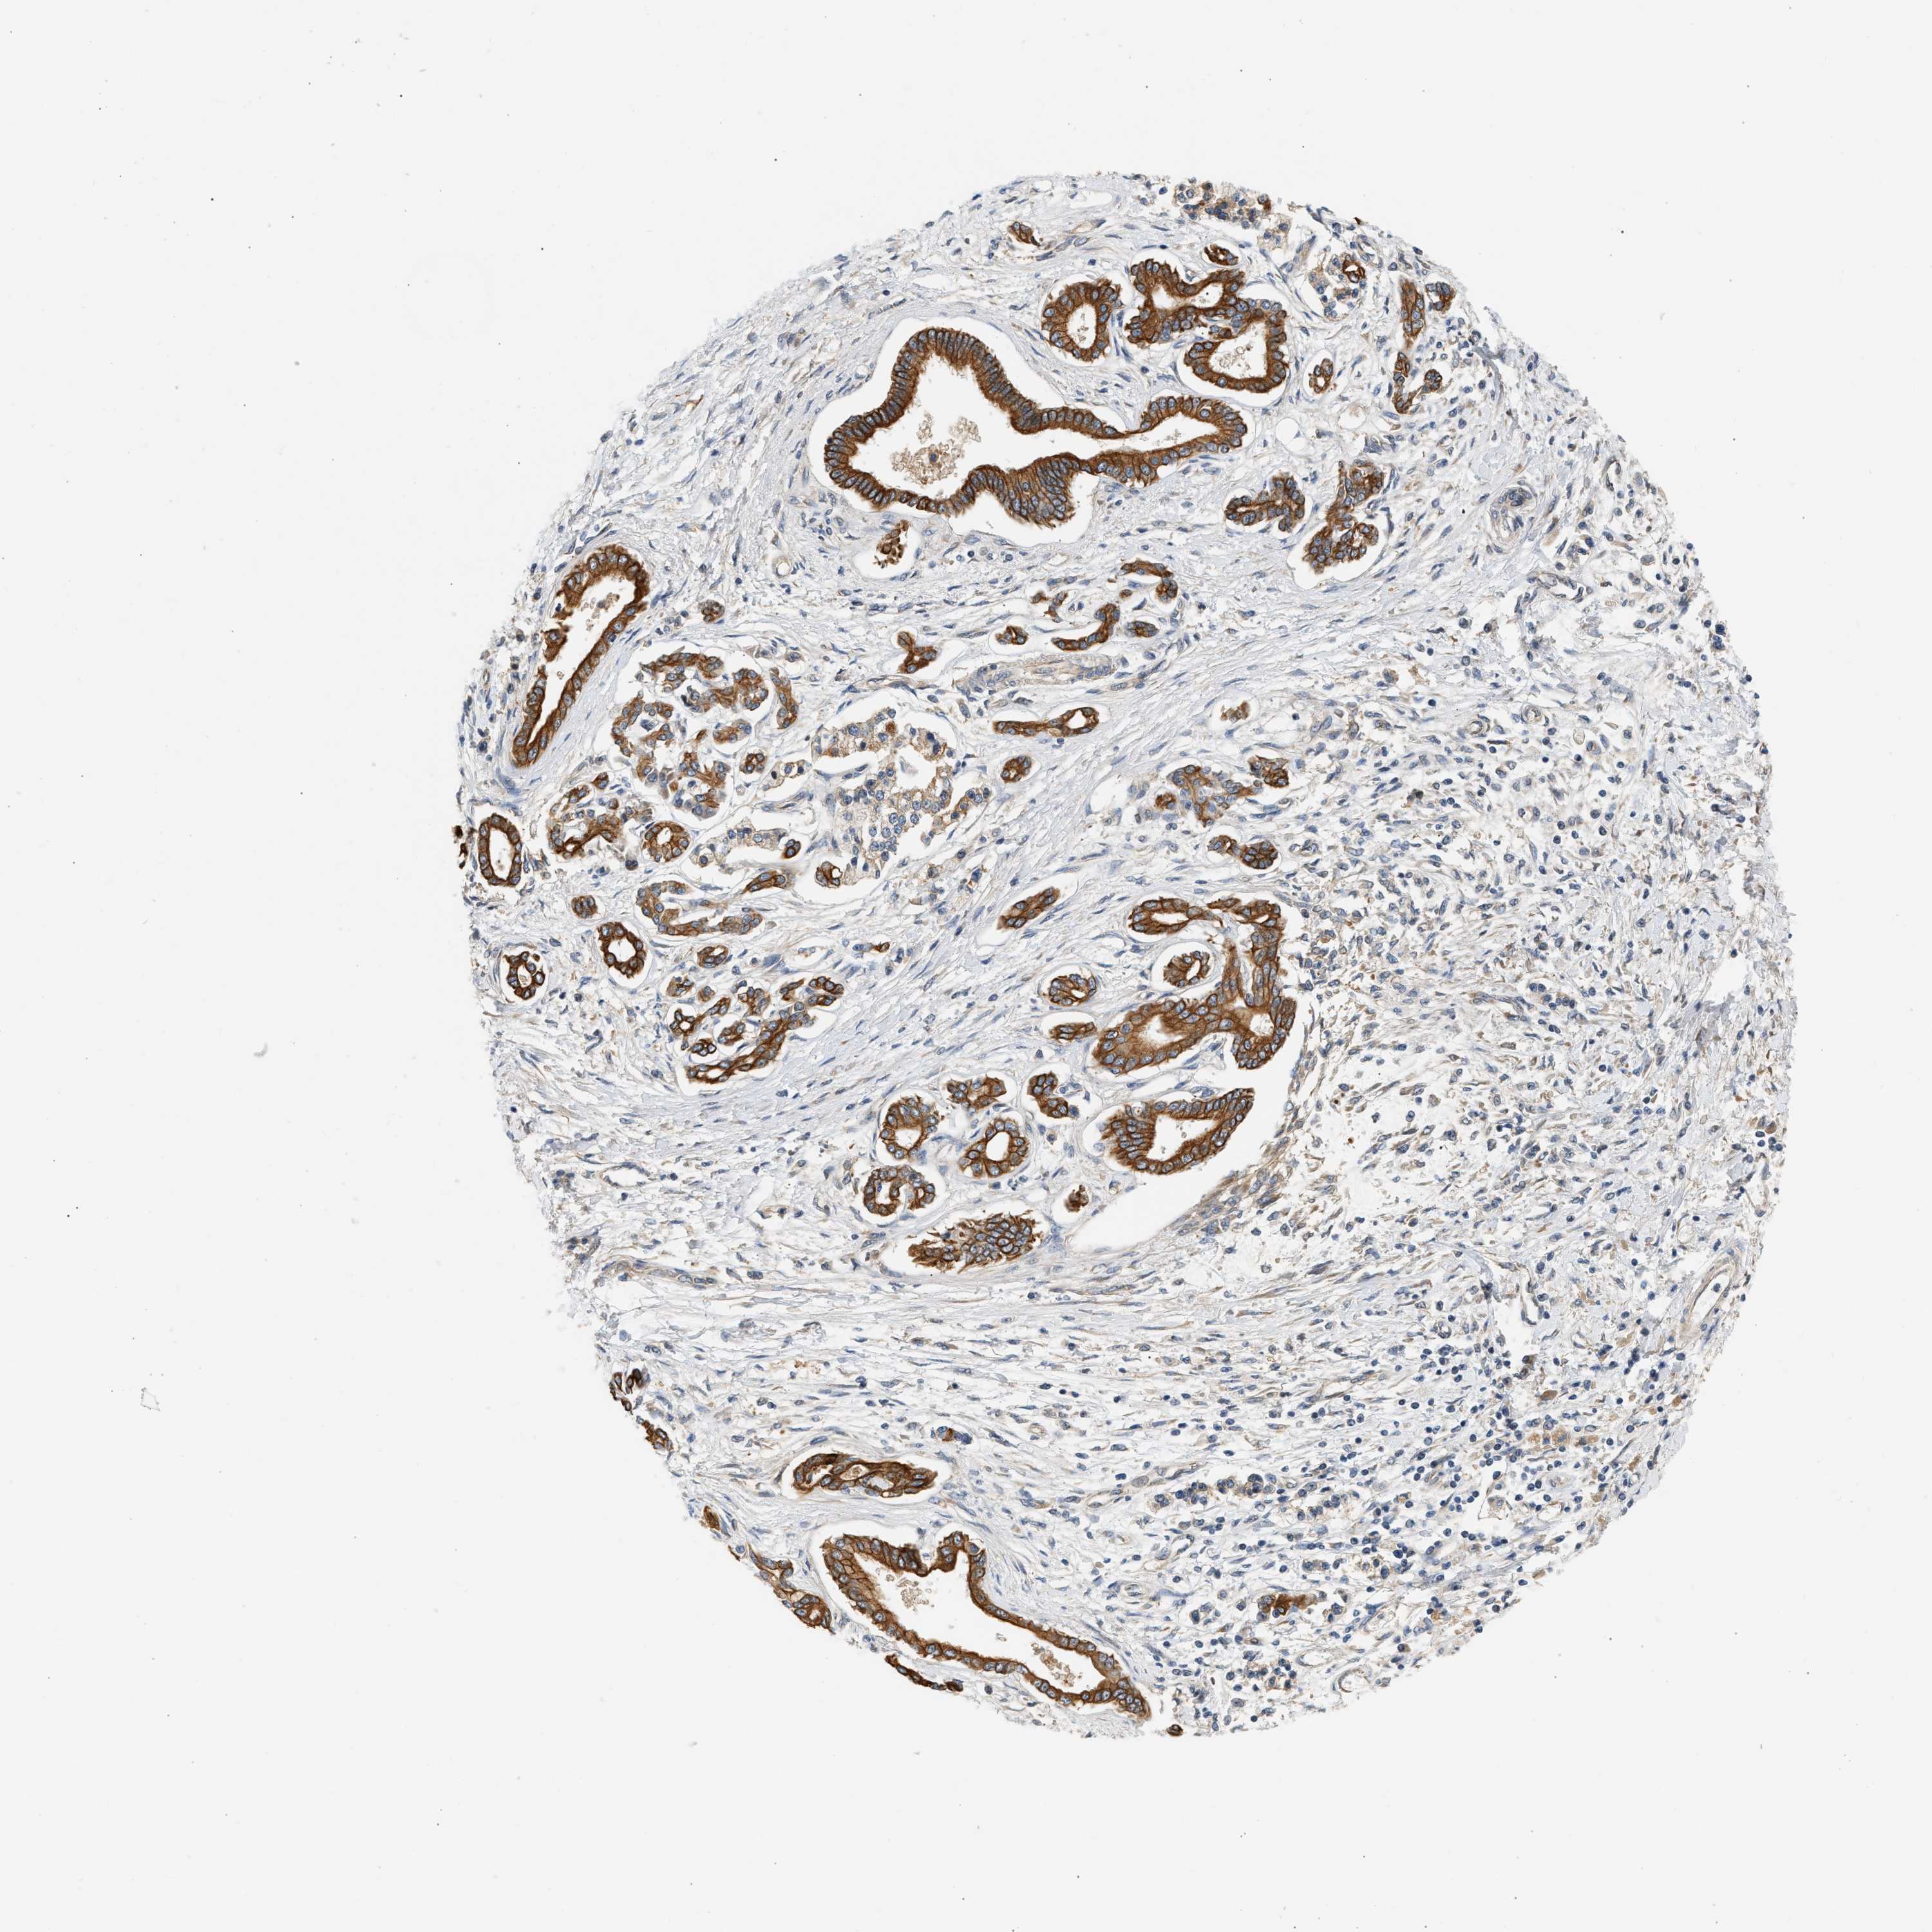

PANCREATIC CANCER - Protein expressioni

A mouse-over function shows sample information and annotation data. Click on an image to view it in a full screen mode. Samples can be filtered based on level of antibody staining by selecting one or several of the following categories: high, medium, low and not detected. The assay and annotation is described here.

Note that samples used for immunohistochemistry by the Human Protein Atlas do not correspond to samples in the TCGA dataset.

Antibody stainingi

Antibody staining in the annotated cell types in the current human tissue is reported as not detected, low, medium, or high, based on conventional immunohistochemistry profiling in selected tissues. This score is based on the combination of the staining intensity and fraction of stained cells.

Each image is clickable and will lead to virtual microscopy that enables deeper exploration of all samples and also displays staining intensity scores, fraction scores and subcellular localization as well as patient and tissue information for each sample.

Antibody HPA019340

Antibody HPA019347

Adenocarcinoma, NOS